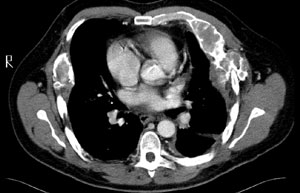

2 Computed tomography scan of the thorax showing multiple rib lesions

Physical examination showed multiple café-au-lait spots with typical “coast of Maine” appearance (Figure 1). Routine laboratory tests gave normal results, except for levels of inorganic phosphate (0.71 mmol/L; reference range, 0.81–1.45 mmol/L) and alkaline phosphatase (286 U/L; reference range, 31–93 U/L). A chest x-ray showed multiple ill-defined radiolucent lesions in the ribs. A computed tomography scan of the thorax showed multiple expansile lytic rib lesions, with a peripheral rim of calcification consistent with polyostotic fibrous dysplasia (Figure 2).